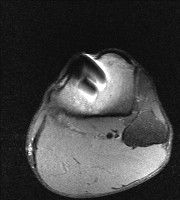

무릎 mri 간단히 봐주실 수 있으시나요 ㅠㅠ

안녕하세요 8년전 십자인대 수술하고 최근 무리한 운동에 무릎 불편감이 생겨서

mri 찍었습니다.

진단결과는 첫 찍은 병원에서 활액막염 이라는 진단을 받았습니다. 혹시 봐주실 수 있으실까요?

올라온 MRI가 단편적이라서 정확한 진단에 어려움이 있지만 십자인대에는 큰 이상이 있지는 않은것 같으며, 무릎관절내 물이 있는 것으로 보아 활액막염의 진단이 맞을 것 같습니다.

하지만 단편적인 영상이기 때문에 촬영병원에서 정확한 판독지 등을 받으시는 것이 좋겠습니다.